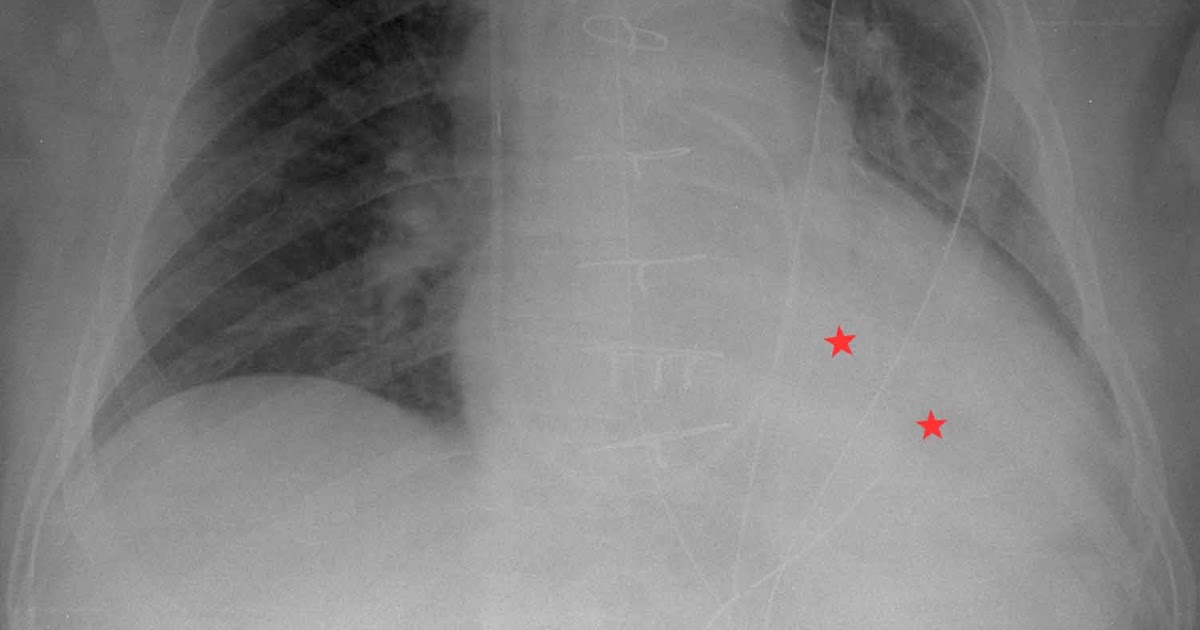

From radiologyinthai.blogspot.com

RiT radiology Large Pleural Effusion Following CABG Post Cabg X Ray Recent data suggest that almost 10% of patients who undergo coronary artery. Patients and healthcare providers must work together after surgery to treat the underlying atherosclerosis and the factors that. Coronary artery bypass grafting (cabg) is a major surgical operation where atheromatous blockages in a patient’s coronary arteries are bypassed with harvested. These clips are placed to prevent flow through. Post Cabg X Ray.